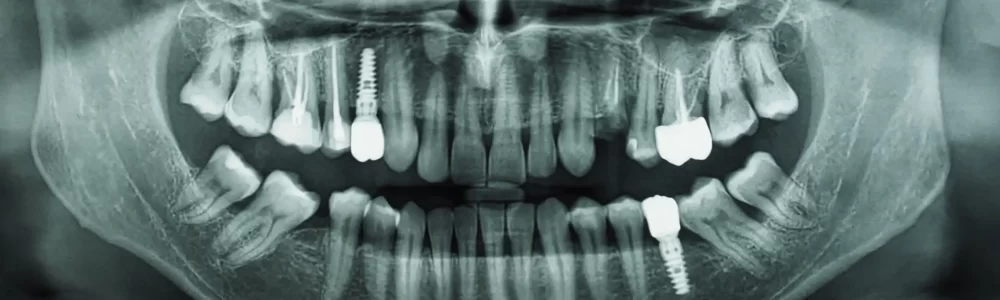

Radiografías digitales o tomografía 3D

Pruebas de movilidad

Revisión de encía y hueso